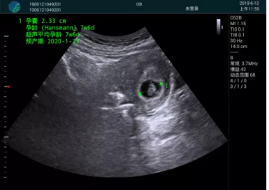

病例一:

清晰顯示孕囊,通過軟件包計(jì)算孕齡7w+6d

M20實(shí)時引導(dǎo),術(shù)中清晰顯示孕囊被破壞和抽吸針的過程,清晰顯示吸引針

抽吸結(jié)束后縱切子宮,孕囊已被完全抽吸,未見明顯殘留

橫切子宮,發(fā)現(xiàn)右側(cè)宮腔靠近宮角處有少許脫模樣殘留

M20引導(dǎo)下,抽吸針找到右側(cè)宮角處再次清掃

二次抽吸后再次進(jìn)行超聲檢查,宮腔未見殘留,宮腔線清晰顯示